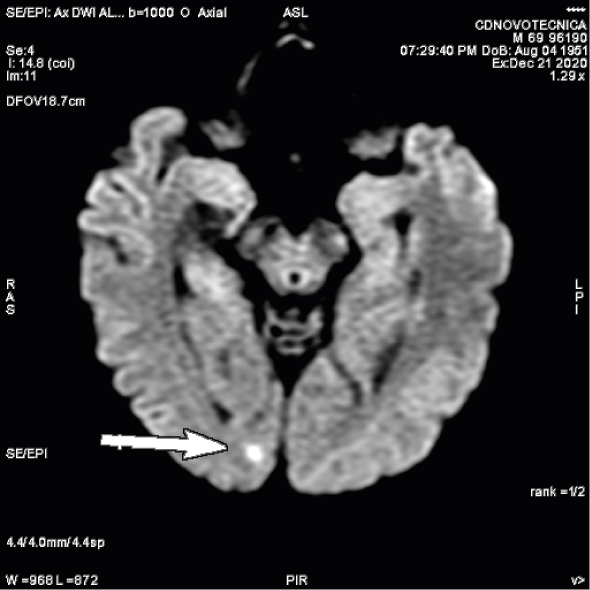

DIFUSIÓN

Clásicamente se empezó a usar la difusión en el estudio del sistema nervioso central y en la actualidad es una secuencia estándar en el estudio cerebral. Inicialmente permitía valorar la isquemia cerebral, pero en la actualidad sus usos son muy diversos, permitiendo también valorar enfermedad neoplásica, patología inflamatoria e infecciosa. En el resto del cuerpo humano básicamente se estudian lesiones tumorales y ayuda en diferenciar lesiones malignas de benignas. Está establecido ya su uso en mama, en próstata y también empieza a utilizarse en otros órganos, por ejemplo, hígado, ovario y útero. Últimamente se está usando como rastreo general en busca de tumores, especialmente metástasis, simulando un PET; es lo que se denomina RM-difusión corporal.

Dentro de su uso en patología inflamatoria, se está investigando su utilización para patología muscular, en la valoración de lesiones deportivas.

Difusión cerebral